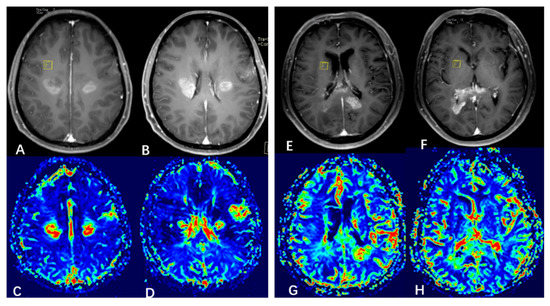

3.2. Probabilistic Fiber Tracking